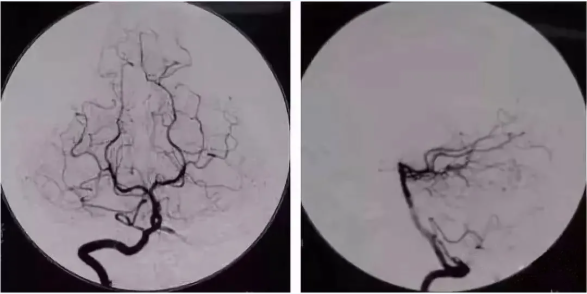

49歲的劉女士因反復(fù)頭暈,多次嘔吐,于8月1日到我院急救醫(yī)學(xué)科就診,行MRI檢查后,初步診斷為左側(cè)小腦半球新鮮腦梗塞、雙側(cè)額葉多發(fā)缺血灶,為進(jìn)一步明確診斷,8月2日醫(yī)院為劉女士進(jìn)行了經(jīng)股動(dòng)脈置管全腦血管造影術(shù),手術(shù)順利,術(shù)中進(jìn)一步明確了腦血管病變。主管醫(yī)師秦文磊指出,劉女士比較幸運(yùn),左側(cè)椎動(dòng)脈末端閉塞,遠(yuǎn)端未見(jiàn)顯影,右側(cè)的小腦后下動(dòng)脈及后交通動(dòng)脈可向左側(cè)小腦半球代償供血,所以劉女士沒(méi)有出現(xiàn)嚴(yán)重的臨床癥狀,術(shù)后可繼續(xù)藥物治療。

經(jīng)股動(dòng)脈插管全腦血管造影術(shù)是應(yīng)用于臨床的一種嶄新的X線檢查新技術(shù),為神經(jīng)科疾病的檢查、治療提供了新的現(xiàn)代化的手段。它是經(jīng)股動(dòng)脈超選擇性插管至靶動(dòng)脈,注入碘對(duì)比劑,通過(guò)數(shù)字減影對(duì)血管進(jìn)行顯象,可清楚顯示頸內(nèi)、外動(dòng)脈、椎基底動(dòng)脈以及腦內(nèi)靜脈,為診斷腦血管疾病提供有力證據(jù),特別是對(duì)于腦血管狹窄、閉塞、動(dòng)脈瘤、動(dòng)靜脈畸形、顱內(nèi)出血等定性定位診斷具有重要的作用。

同時(shí)也是顱內(nèi)血管介入治療技術(shù)的基礎(chǔ),明顯優(yōu)于頸動(dòng)脈彩超、顱腦CTA、MRA等檢查手段,在臨床中廣泛應(yīng)用,被認(rèn)為是腦血管病變判定的“金標(biāo)準(zhǔn)”。